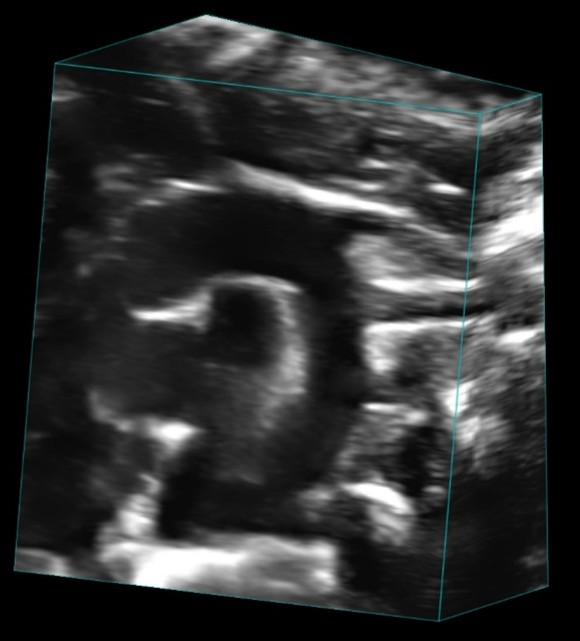

- 3D/4D Imaging for volumetric and dynamic visualization

Custom services Embryo Sonography (Fetal Sonography)

Gravidity check

Ultrasound confirms pregnancy in rodents from E6.5 onward, when external signs are not visible. We offer three levels:

- Standard – Basic check with 2D imaging.

- Counting – Check plus accurate embryo counting via 3D scan.

- Assessment – Full evaluation: vitality, counting, 3D imaging, Doppler.

Benefits: Early detection reduces animal use, prevents unnecessary euthanasia after miscarriage, and accelerates projects by enabling timely re-mating when pregnancy is not confirmed.

Fetal Echocardiography

For developmental studies, it is possible to monitor living mouse/rat embryos in uterus and follow the development of cardiac structures as well as changes in blood flow velocities in the heart and umbilical artery. An application of high-frequency probes with conventional 2D and pulse-wave Doppler imaging of the fetus can provide excellent information on the early development of cardiac structures.